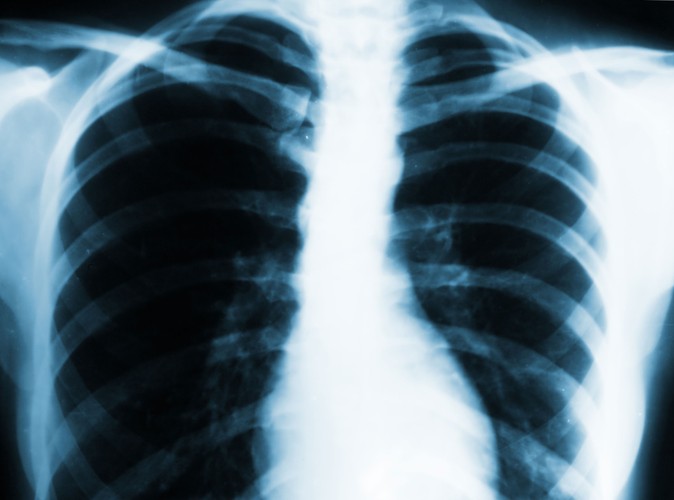

2 Zdaniem ekspertów, w Polsce spada zapadalność na gruźlicę, a liczba nowych zakażeń nie jest wysoka. W naszym kraju rocznie notuje się około ośmiu i pół tysięcy zachorowań na gruźlicę